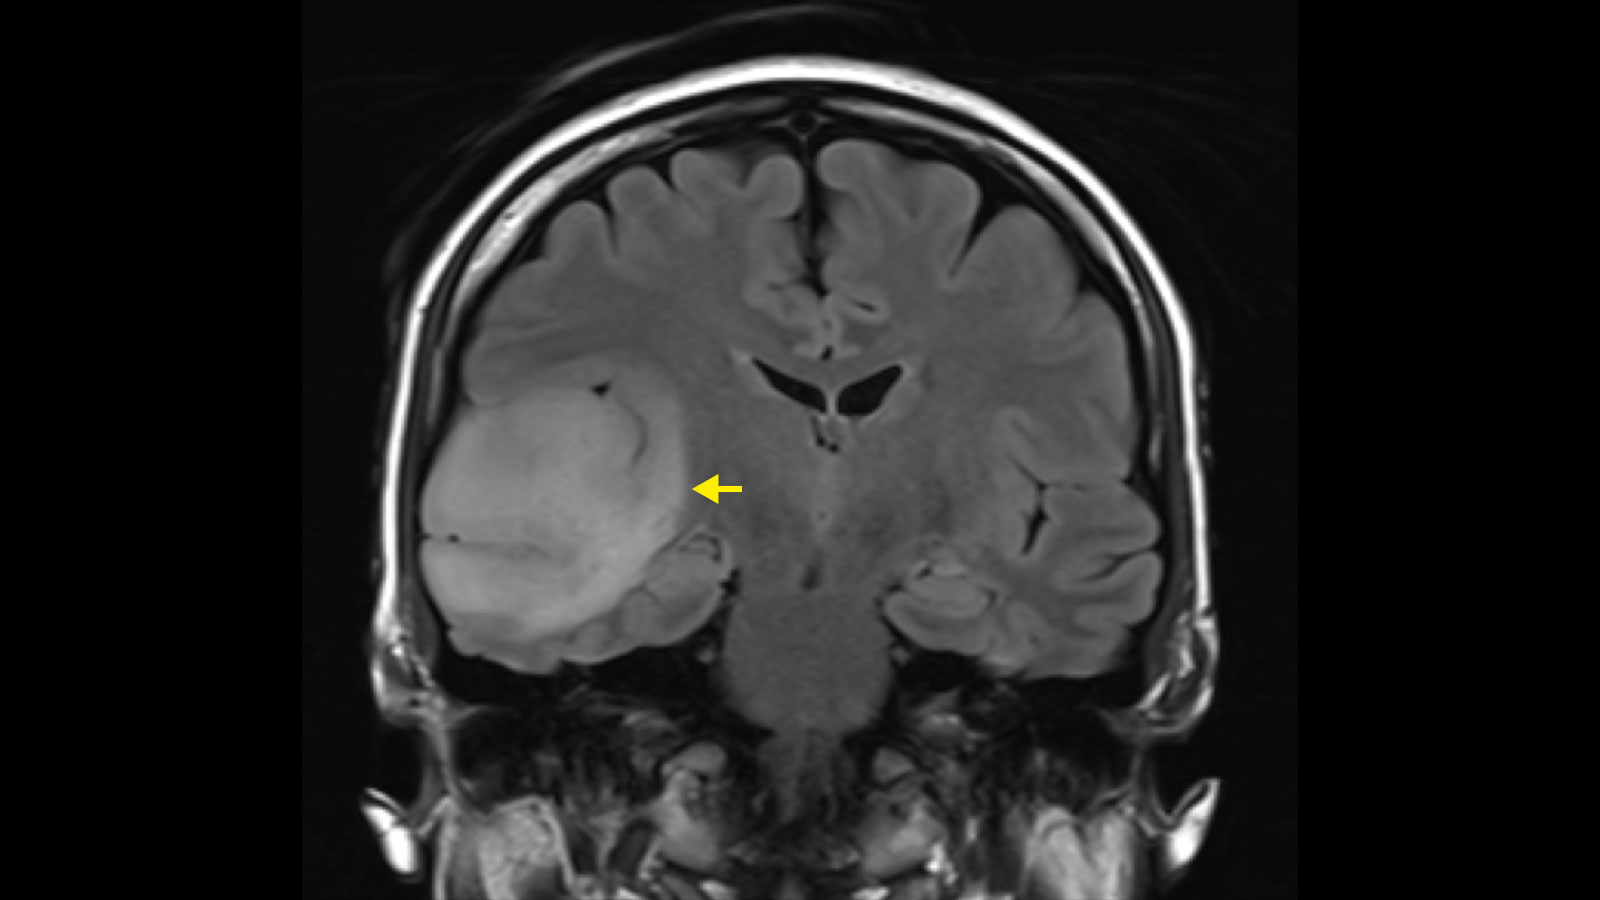

Surgery

Surgery is the initial step in a brain cancer treatment plan, with the primary goal of removing as much of the tumor as safely as possible. The extent of the procedure depends on the tumor’s size, type, and location. While complete removal is the goal, it is not always possible if the cancer is near viable brain structures. Because of that reason, surgery is often combined with other therapies to address any remaining cancer cells.